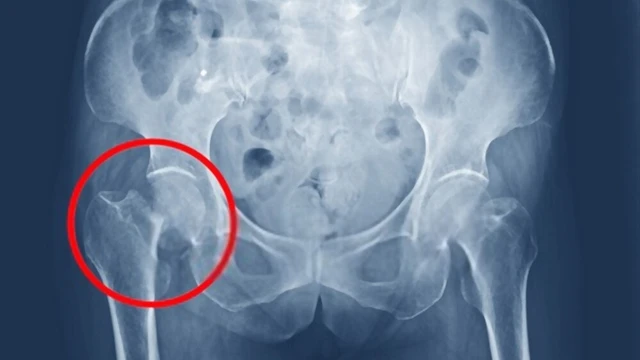

Hẹp khe khớp háng có thể được phát hiện trên hình ảnh X-quang. Ở một khớp khỏe mạnh, có một khoảng trống bình thường giữa các đầu xương tạo thành ổ khớp. Các đầu xương trong khớp được bao phủ bởi sụn khớp. Ở một khớp không khỏe mạnh (bị ảnh hưởng bởi các tình trạng gây viêm khớp) có bằng chứng về sự thu hẹp khoảng cách giữa các đầu xương trong khớp (hẹp khe khớp) do mất sụn.